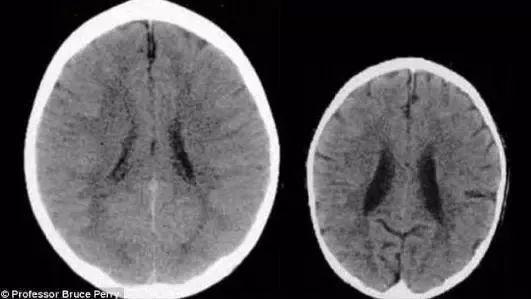

更加直接的证据是一张大脑扫描图,

扫描图上显示的是两个3岁孩子的大脑:

从这张扫描图上可以明显的看出来,

左边的大脑要比右边大得多,

而且黑暗的区域更少。

神经学家解释,

右边的孩子大脑容量缺少的部分,

很可能导致他缺少一些能力。

比如没有那么聪明,缺少同理心,

也更容易在学业、事业、精神健康方面遇到问题。

造成这种差距的真正原因,

就是两个孩子的母亲不同的对待孩子方式。

左边孩子的妈妈

一直给予孩子温柔的爱抚和积极的回应。

右边孩子的妈妈则经常让孩子遭受忽视和打骂。